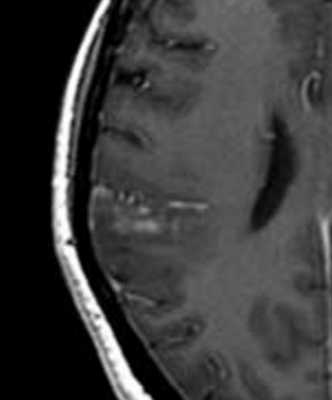

МРТ головного мозга. Т1-взваешенная МРТ с контрастированием. Менингиоангиоматоз.